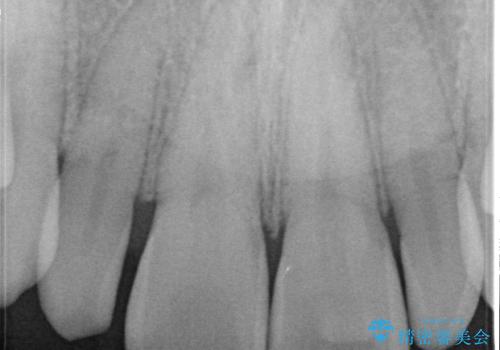

- 当院で矯正治療を行っており、上の前から2番目の歯の形も気になるので治したいと希望がありました。

矮小歯といわれる通常よりも小さい歯であったので、こちらにオールセラミッククラウンを装着して自然な歯の形にすることにしました。

上の前から2番目の歯を少量削らなければならないデメリットはありますが、クラウンの装着により自然な形へすることができました。